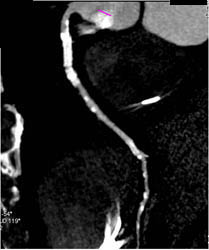

Diseased LAD